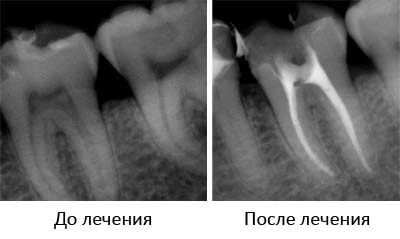

Лечение острого гнойного пульпита и хронических форм заболевания включает:

- полное удаление (экстирпацию) воспаленных мягких тканей,

- механическое расширение каналов,

- их антисептическую обработку и пломбирование.

При девитальной экстирпации (полном удалении пульпы после её умерщвления) лечение осуществляется в два посещения. На первом этапе под местной анестезией врач вскрывает пульпарную камеру и накладывает специальный препарат, вызывающий гибель пульпы.

Удаление пульпы, герметизация каналов, а также постановка пломбы проводится во время второго визита пациента.

Витальная экстирпация (удаление коронковой и корневой части измененной пульпы под анестезией) позволяет провести лечение в одно посещение. Пациенту делают местную (проводниковую + инфильтрационную) анестезию, после чего полностью удаляют воспаленную ткань, обрабатывают каналы и ставят постоянную пломбу.

В ходе лечения обязательно следует сделать не менее двух рентгенологических снимков. Первый позволяет перед началом работы установить длину, ширину и направление каналов. Повторная рентгенография проводится после герметизации каналов (но до постановки постоянной пломбы!) для того, чтобы оценить качество работы.